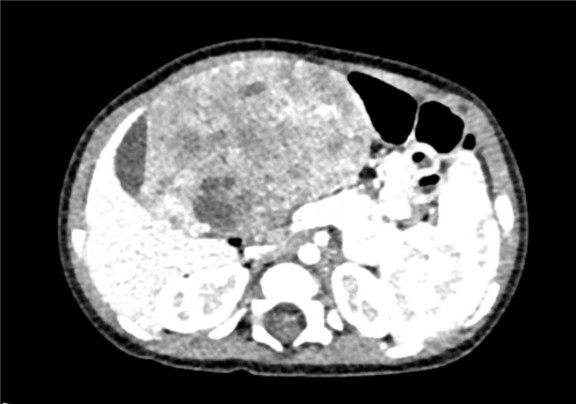

术前CT检查:

动脉期

静脉期

将0.625mm双源薄层CT资料的静脉期和动脉期Dicom格式文件导入海信CAS系统。

通过调节窗宽窗位调整CT序号,对肝实质,胆囊,下腔静脉,肿瘤,肝动脉、门静脉及肝静脉等进行三维重建;系统自动计算肝脏体积。

模拟手术操作,自动计算切除肿瘤体积。肝脏体积为310.9ml,肿瘤体积为437.7ml,肿瘤体积是肝体积的1.4倍,通过比对9-12月正常肝脏体积为321.13±118.91ml,通过术前模拟手术,精准判断切除后剩余肝脏体积能耐受,避免肝衰竭发生。